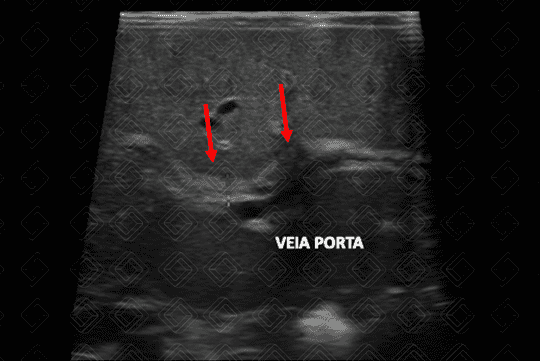

Texto alternativo para a imagem Figura 3. Créditos: Dra. Elazir Mota - Rio de Janeiro/RJ

Descrição da lesão: Atresia de vias biliares. Ultrassonografia do abdome evidenciando vesícula "atrésica" (eixo longitudinal < 15 mm e com contornos irregulares) (figuras 1 e 2), cordão hiperecogênico anterior à bifurcação da veia porta (figura 3), esplenomegalia e ascite (figura 4).

• Cordão hiperecogênico: corresponde aos ductos biliares obliterados por fibrose, se traduzindo por hiperecogenicidade tubular ou triangular, devendo sua espessura ser mensurada anteriormente à bifurcação da veia porta, com valores considerados positivos acima de 3 mm, de 3,5 mm ou de 4 mm;